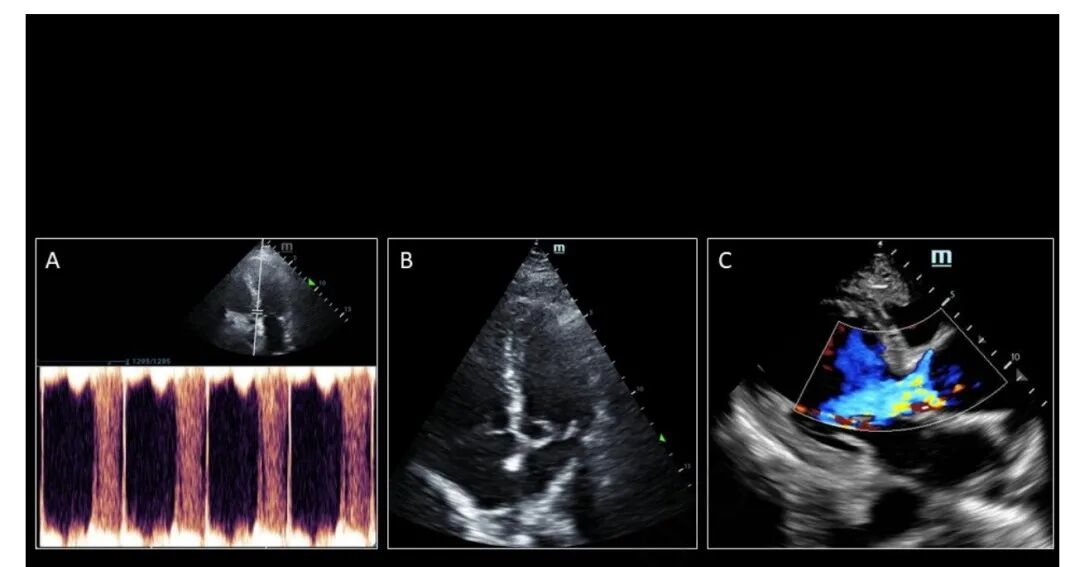

4. 脉冲波 (PW) 多普勒用于利用小样本量获得接近 AV 的 VTI,并优化 VTI 包络以进行跟踪(图 2A)。

7. 放大并测量 LVOT 直径,从收缩早期到中期的内缘到内缘,就在 AV 近端(图 2B)。

图 2. 使用 (A) A5c 视图中从 LVOT 近端到主动脉瓣的 PW 多普勒样本的 VTI 跟踪,和 (B) 测量 LVOT 直径的 PLAX 来评估每搏量